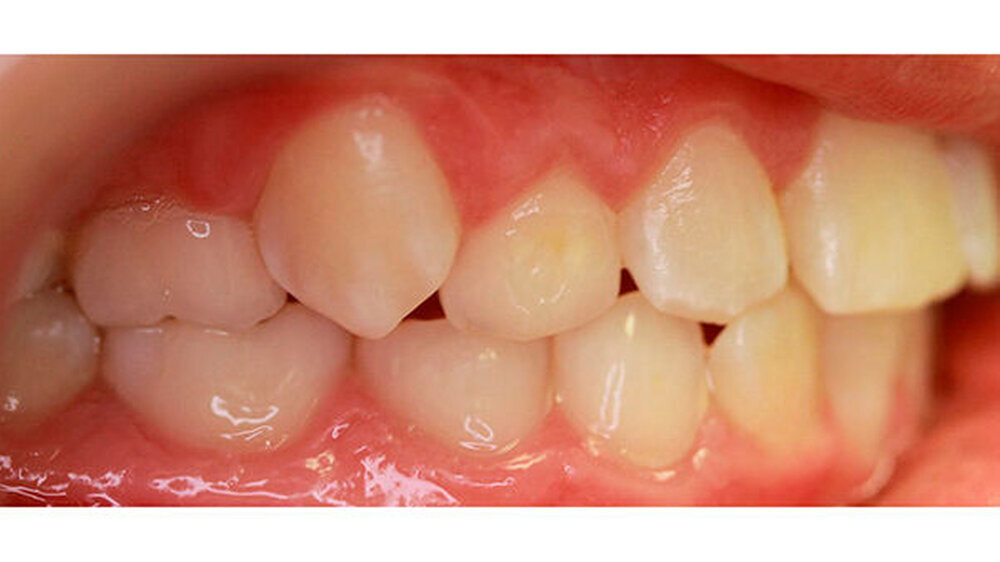

Im Rahmen der Modellanalyse ergaben sich folgende Befunde: Im Oberkiefer lagen außer der Transposition der Zähne 13 und 14 multiple Rotationen und Kippstände vor. Die Unterkieferfront wies einen Engstand auf. Im Molarenbereich lag beidseits eine Distalokklusion von ¼ Prämolarenbreite vor. Der Overjet betrug 2 mm, der Overbite 3 mm. Die Zähne 22/33, sowie 24/74 wiesen eine Kopfbissrelation auf.

Der Therapieplan sah die chirurgische Freilegung von 14 und 23 vor, deren Einordnung in den Zahnbogen, die Beseitigung der Transposition zwischen den Zähnen 13 zu 14, sowie die Herstellung einer gesicherten Seitenzahnokklusion mit regelrechter sagittaler und vertikaler Frontzahnstufe.

Nach dreijähriger kieferorthopädischer Behandlung konnte die Patientin entbändert werden. Eine Stabilisierungsphase mit herausnehmbaren Essixschienen folgte. Nach Ende der aktiven Behandlungszeit waren die Therapieziele weitgehend erfolgreich umgesetzt worden.